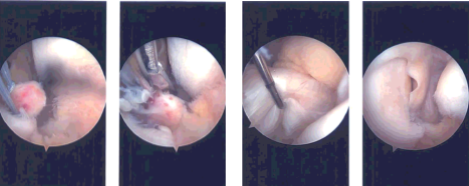

Once the FlipCutter was in, it was flipped and a 5 mm gutter was made for the meniscus to sink in. A passing loop was passed through the tunnel and retrieved. The FiberWire were passed through the passing loop unto the tunnel and brought out near the tibial tuberosity. A good reduction of the meniscus would be seen and pictures were taken and saved.

Intraoperative Arthroscopy Images

The sutures were ported into the tibia with the use of a 4.75 SwiveLock after drilling and tapping. A good reduction and fixation of the meniscus root was achieved. Examination of the intercondylar notch showed an intact ACL. E